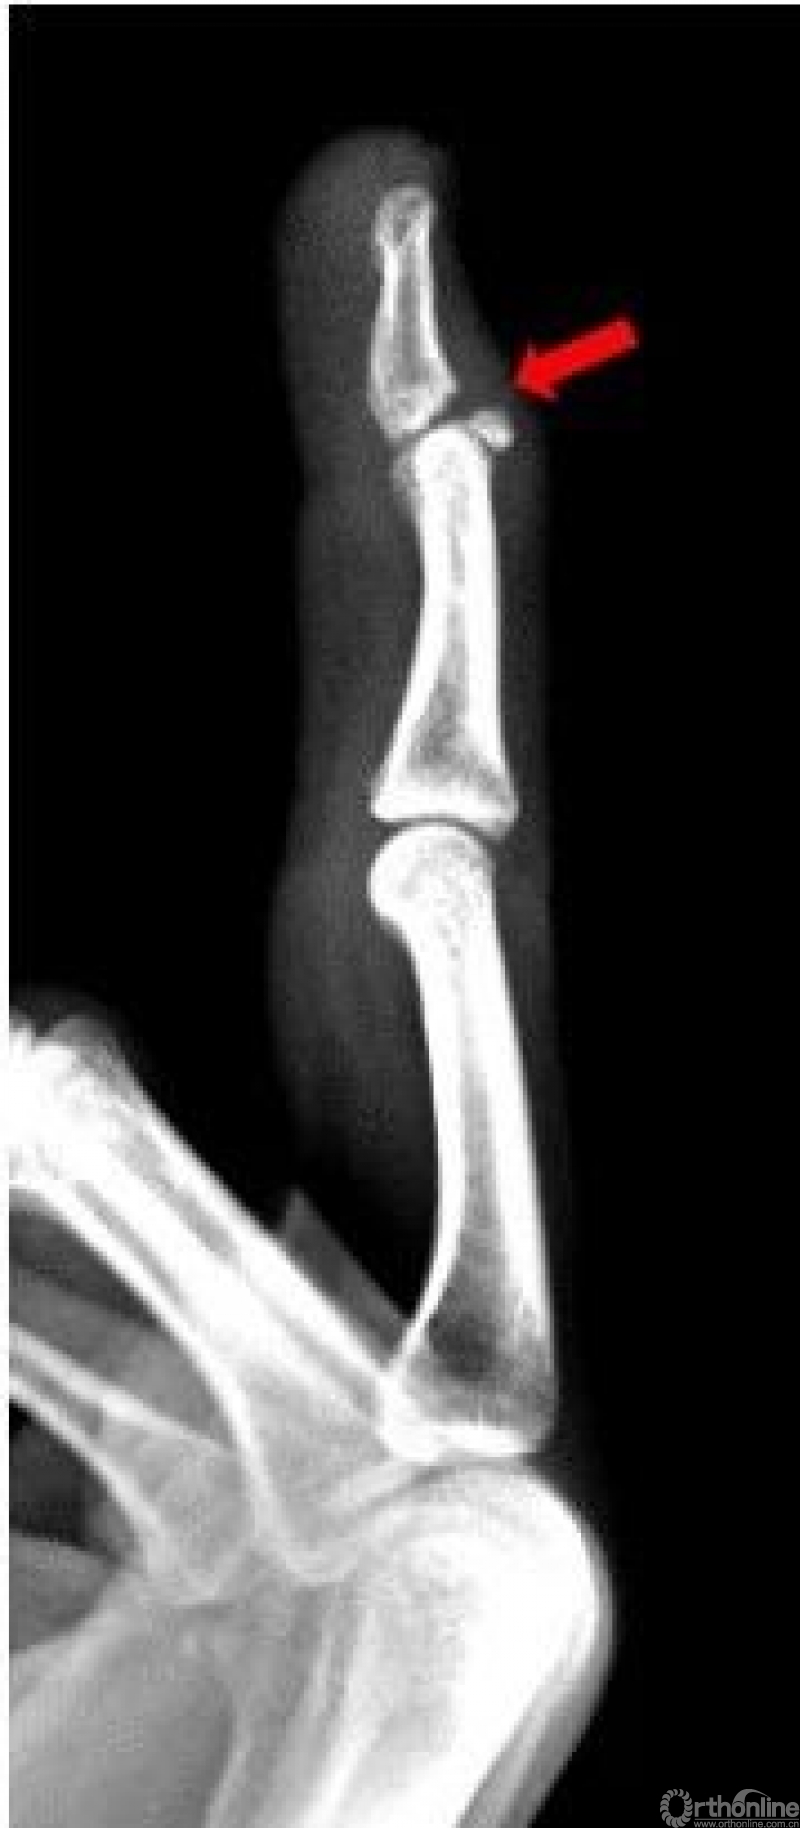

右手中指远节近端背侧关节处见游离骨片影。右手中指远节骨折